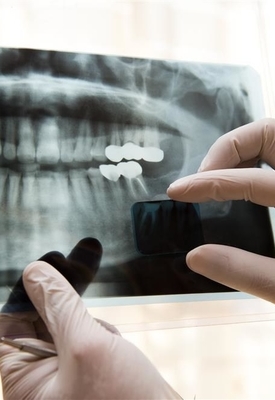

一个牙洞用好的修补多少钱

补牙材料有玻璃离子水门汀(价格100-300元左右一颗牙洞适用于乳牙或低龄儿童后牙简单龋洞等)、复合树脂材料(普通复合树脂200-500元一颗牙洞适用于前牙和后牙中等复杂程度龋洞等、美学树脂500-1000元甚至更高一颗牙洞适用于前牙美观要求极高情况),影响价格因素有牙洞位置(后牙修复价相对前牙可能低,前牙复杂龋洞等因美观等原因价更高)、地区差异(一线城市牙科诊所或医院补牙价通常比二线、三线城市高)、医院等级(三甲医院补牙价一般高于二甲医院),一般人群补牙后24小时内避免用补牙侧咀嚼食物等,前牙美学树脂修复24小时内尽量避免吃染色深食物,成年人补牙后要保持口腔卫生定期复查,儿童补牙后家长要看护好防止材料脱落等且饮食避免过硬过黏食物要监督刷牙等,孕妇补牙要告知医生怀孕情况选择对胎儿影响小的治疗方式且补牙后要加强口腔清洁。